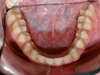

Vues avant le traitement